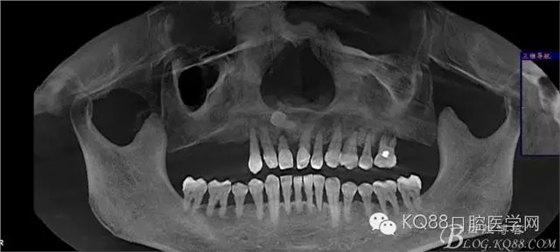

輔助檢查:ct示骨密度良好,11 12區(qū)域骨下有一水平向埋伏牙,15 16區(qū)域骨高度2.5-3mm,骨寬度6-9mm。

治療計劃:11 12 13及埋伏牙拔除,同期上頜竇外提升手術(shù)及種植修復(fù)